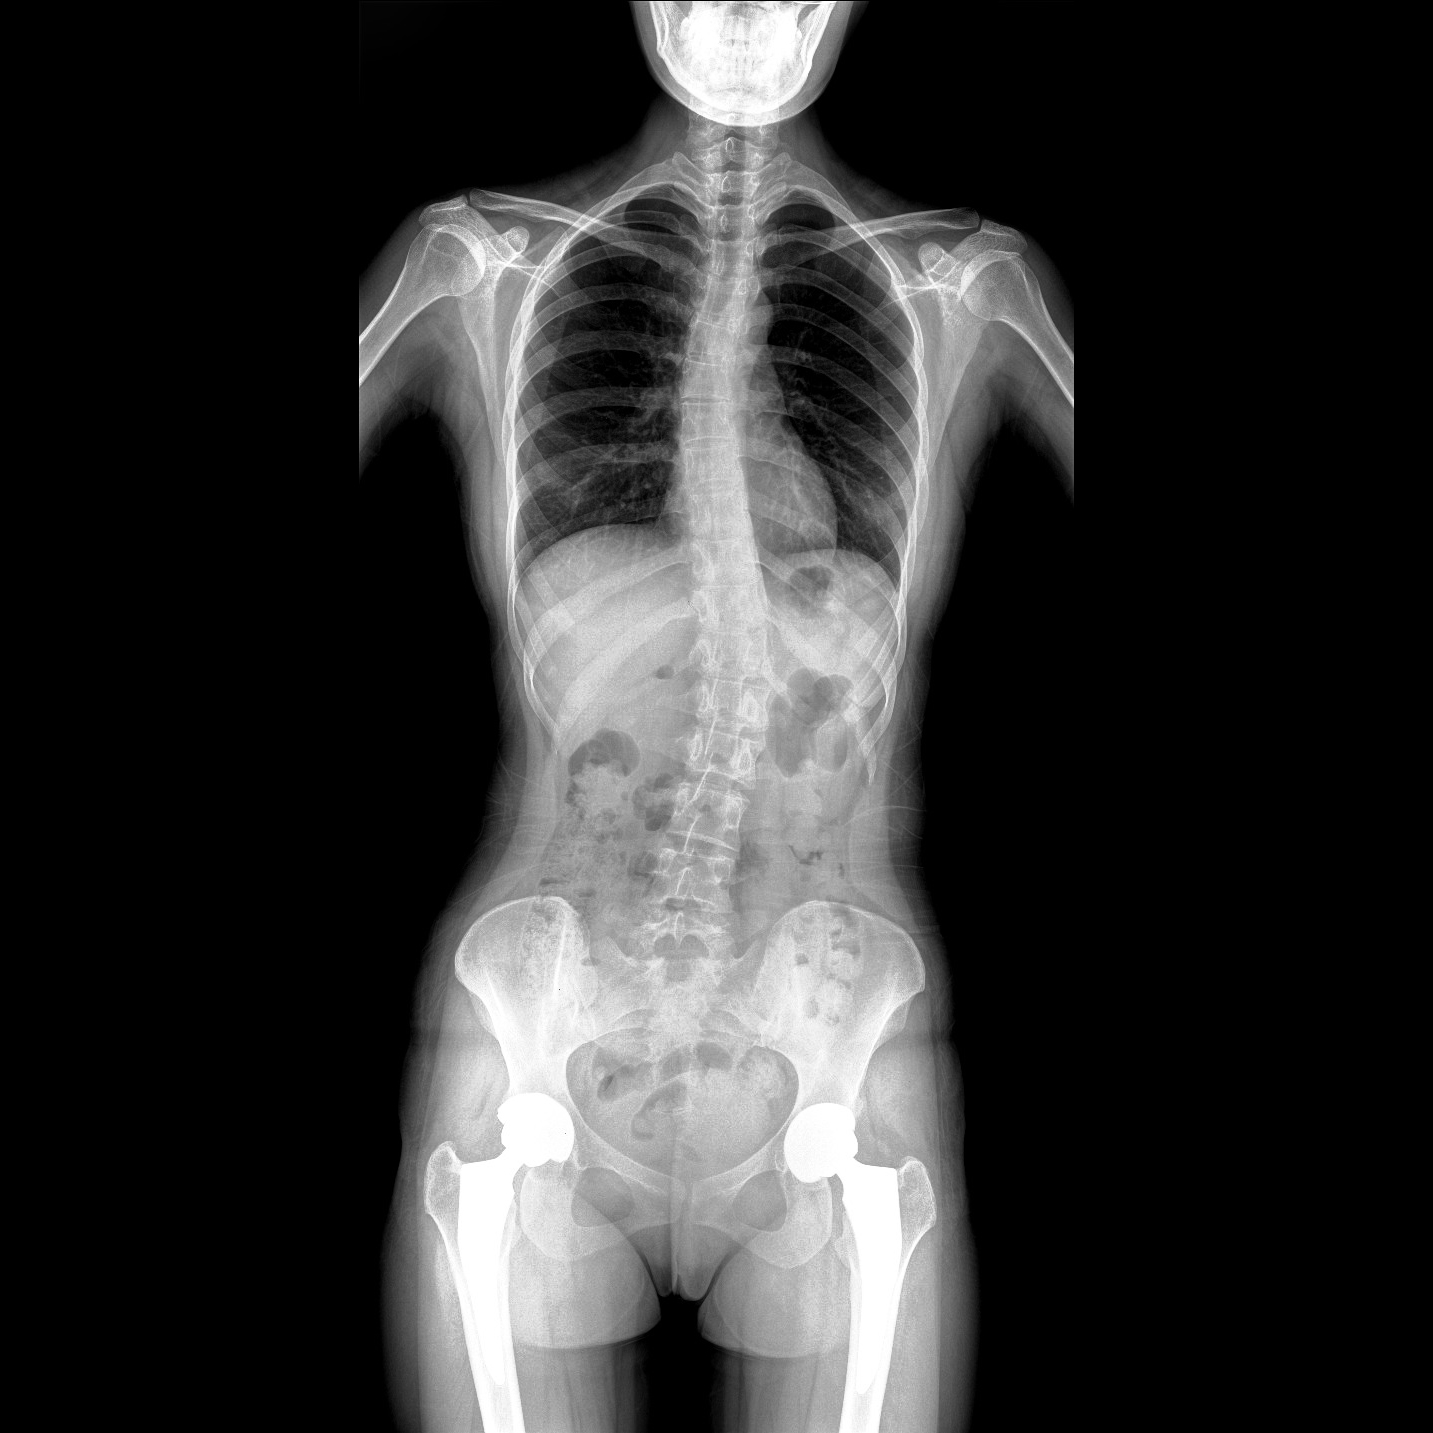

支持全脊柱攝影、雙下肢攝影、脊髓造影、復(fù)雜創(chuàng)傷、人工關(guān)節(jié)置換、關(guān)節(jié)損傷的修復(fù)重建等大視野臨床應(yīng)用

17"*34"有效視野,一次成像不拼接。相較于多張攝影再軟件拼接的DR設(shè)備,PLX8600解決了拼接圖像存在密度不均勻,拼接處圖像配準(zhǔn)和放大效應(yīng)等問題,給臨床帶來了大視野影像解決方案,可一次性覆蓋全脊柱或雙下肢影像。